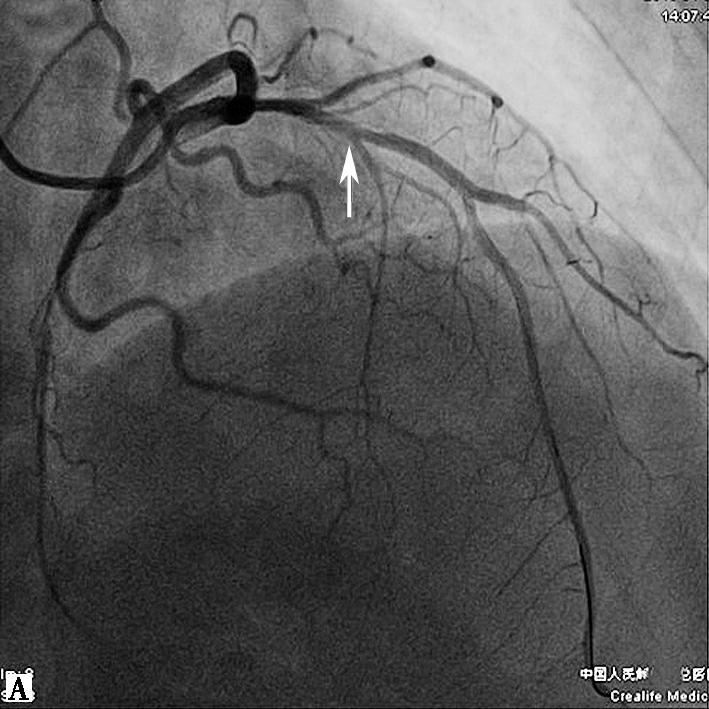

给予双联抗血小板、调脂、控制心率、抗心衰及泼尼松龙60mg每日1次,并皮下注射依诺肝素强化抗凝,1周后复查心脏超声(图2),发现右房内疑似血栓影完全消失,患者也无低氧、咯血等肺栓塞临床表现。后完成CAG +光学相干成像(OCT)检查(图3),提示:左优势型,前降支近段管腔不规则发白,考虑血栓影,管腔分支稀少,血流TIMI 3级;回旋支远段节段性狭窄达90%,血流TIMI 2级;右冠细小。

图3冠脉造影结果

我院造影图像:A图显示前降支血流稍慢,中段可见管腔发白,怀疑血栓影;B图提示回旋支远段重度狭窄90%,血流TIMI 2级